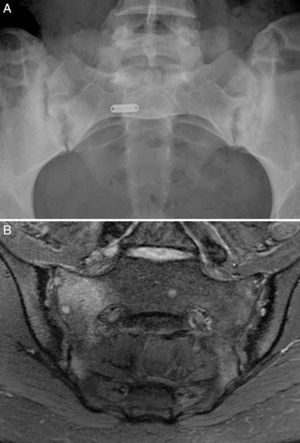

Case no. 1: a 28-year-old woman with a 10-year history of chronic inflammatory low back pain and asthenia. Plain radiography revealed evident bilateral sacroiliitis. Magnetic resonance images (MRI) of the sacroiliac joints showed the following signs of sacroiliitis: sclerosis, erosions and marked bilateral periarticular bone marrow edema (Fig. 1). As she was HLA-B27-positive, a diagnosis of ankylosing spondylitis was established. She had a sister with CD. She had no associated gastrointestinal symptoms. Serological tests for CD, consisting of screening for anti-tTG and anti-deamidated gliadin peptide antibodies, both IgG and IgA, was negative. HLA typing demonstrated that she was homozygous for DQ7 and the absence of DQ2 and DQ8. The duodenal biopsy revealed intraepithelial lymphocytosis with 37 CD3+ lymphocytes per 100 enterocytes, without villous atrophy. There was a clear improvement in low back pain and asthenia 3 months after initiating the GFD. At 10 months, her chronic low back pain had resolved, but recurred after inadvertent gluten ingestion.

Case no. 1. (A) Radiography of sacroiliac joints showing widening, erosions and bilateral sclerosis, which corresponds to bilateral grade 3 sacroiliitis. (B) Magnetic resonance image of sacroiliac joints showing sclerosis, erosions and marked bone marrow edema, all signs of active sacroiliitis.